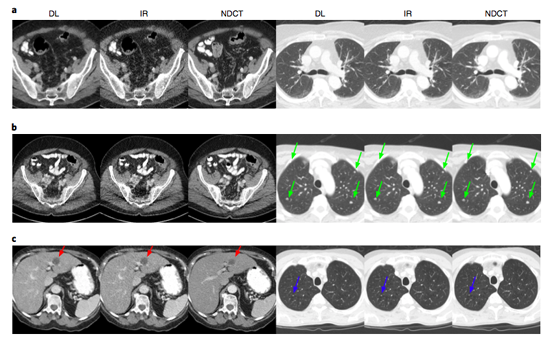

Для оценки эффективности работы алгоритма ученые использовали томограммы брюшной полости и легких 60 пациентов. Четыре вида томограмм (стандартную КТ, полученную при высокой дозе излучения и низкой, изображение, восстановленное с помощью коммерчески доступного метода статистической итеративной реконструкции) дали оценить троим радиологам. Как сообщают ученые, специалисты сошлись на том, что реконструкция изображения с помощью нового метода работает либо также хорошо, либо чуть лучше итеративной реконструкции в том, что касается избавления от шума и артефактов. В том, что касается определения опухолей и повреждений по томограммам, новый метод показал чуть большую эффективность.

Изображения, полученные с помощью нового алгоритма (DL), итеративной реконструкции (IR) и при стандартной дозе излучения. Красными стрелочками отмечены повреждения печени, зеленым — уплотнение стенки легкого, а синим — эмфизема.

Несмотря на эффективность предложенного метода, сравнимую с уже существующими, у алгоритма есть ряд недостатков. Во-первых, пока что он работает только применительно к двум областям тела человека — брюшной полости и легким, и для улучшения его работы нужно собрать и использовать для обучения больше данных. Во-вторых, с помощью нового метода не удалось обнаружить две из 30 опухолей в брюшной полости, которые были в датасете — точно так же, как и с помощью других методов. При этом новый метод работает быстрее и сравнимо эффективнее уже использующихся.